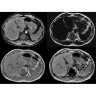

• Комплексная оценка печени — первая в отрасли ИП MR-Touch открывает новые возможности диагностики благодаря способности определять различия в жесткости тканей.

МР-эластография: неинвазивная методика комплектной оценки печени

Пациентам с такими хроническими заболеваниями печени, как фиброз и цирроз, часто требуется регулярное наблюдение гастроэнтеролога. Это может потребовать проведения инвазивных процедур, которые не всегда позволяют получить полную информацию о состоянии печени.

Новая ИП MR-Touch, разработанная компанией GE совместно с клиникой Майо, основана на исследовании печени с помощью акустических волн, в ходе которого выявляются различия в жесткости тканей. Результатом исследования является эластограмма, полное изображение печени. По таким эластограммам радиологи и гастроэнтерологи могут периодически контролировать состояние пациента и принимать информированные решения о терапии. Более того, данная методика открывает новые возможности и позволяет оказывать инновационные услуги имеющимся пациентам и привлекать новых клиентов.